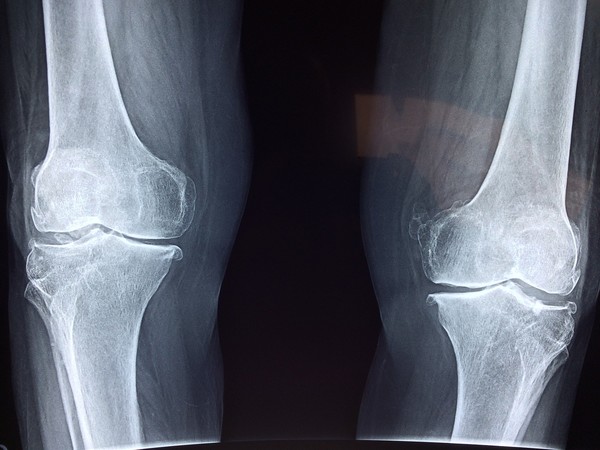

국내에 유통되는 인체조직이 3년간 꾸준히 증가한 것으로 나타났다. 이들 대부분은 '뼈'가 차지했다.

지난해 국내에서 유통된 인체조직은 뼈가 667,379개(77%)로 가장 많았으며, 피부(155,339개, 18%), 건(19,614개, 2%), 양막(10,192개, 1%)이 그 뒤를 이었다.